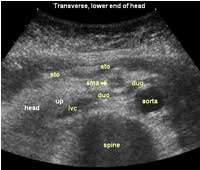

The following study describes anatomical landmarks in the ordinary pancreas of a thin patient:

Transverse planes in caudal direction:

![]() Image04 |